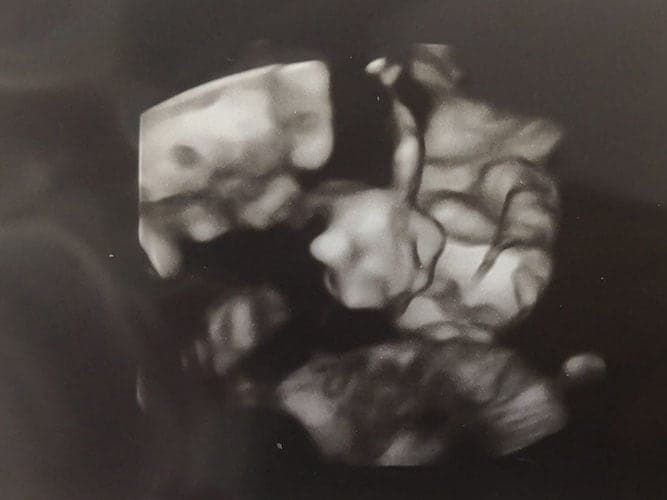

Ultraschallbilder aus dem 3. Trimester (29. bis 40. SSW)

Im dritten Trimester der Schwangerschaft ist das Baby so groß, dass es nicht mehr komplett auf ein Ultraschallbild passt. Nun kann man wunderbare 3D-Ultraschalle des Gesichts machen. In diesem Semester nehmen die Babys nochmal rasant zu und wer Glück hat, kann auf seinem Ultraschall schon erste Gesichtszüge erkennen.

Wer sich jedoch erhofft Gesichtszüge zu erkennen, der wird oft enttäuscht. Zwar kann man beim 3D-Ultraschall schon eine Menge sehen, aber das umgebende Fruchtwasser sorgt in den allermeisten Fällen für starke Störungen.